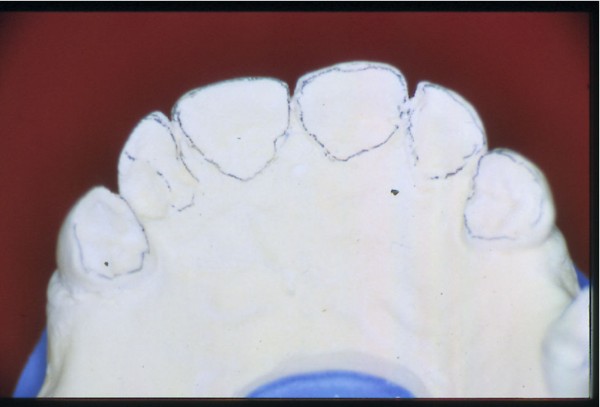

Entidades patológicas como el bruxismo, limitan la terapéutica odontológica y las certezas de un pronóstico favorable y prolongado en el tiempo. El strees, factor predisponente, y alteraciones morfológicas en la oclusión que impiden la disclusión de los sectores posteriores durante las excursiones de la dinámica mandibular, o factores desencadenantes. Caso Clínico Mujer , 53 años, derivado por especialista en Cirugía Máxilo Facial, con evidentes signos de hipertrofia de ambos maseteros. Clínicamente la carencia de las puntas caninas de ambos lados de ambas arcadas, nos habla de ciclos masticatorios eminentemente horizontales, tipo rumiante, donde el fenómeno de DOBLE DESGASTE de las cúspides estampadoras se pone en clara evidencia.(Fig.3 y 4 ) Ambos fenómenos(desgaste exagerado y extrusión dentaria nos habla de una invasión del espacio del maxilar superior, mediante la elevación del inferior, con las lógicas consecuencias musculares por acortamiento: Hipertrofia, acúmulo de ácido láctico, sobrecarga de los elementos tendinosos y capsulares, etc. Se le hace saber al paciente acerca de la necesidad de múltiples técnicas de Rehabilitación ANTES de llegar a reponer sus piezas perdidas. Se le pone en conocimiento de la necesidad de reponer SOLO hasta su primer molar, el que se reemplazará mediante una PREMOLARIZACIÓN, dado que el ancho de su cresta no permite reemplazar un primer molar salvo con riesgos de invadir el ESPACIO BIOLÓGICO necesario para un buen desarrollo de sus funciones. Es necesario tener en cuenta, que la pérdida de dimensión vertical por excesivo desgaste de la porción coronaria es siempre acompañada, por un descenso de las estructuras corticales, desfavoreciendo la relación CORONO/RADICULAR, lo que hace fundamental el ejercicio de unas fuerzas oclusales VERTICALES, a fin de no aumentar la movilidad de las piezas, una vez que la altura adecuada haya sido restablecida, verticalidad que solo se alcanzará mediante la implementación de una GUÍA ANTERIOR adecuada. Se estudia el caso clínicamente y se toman modelos de estudio debidamente montados en articulador semi ajustable en posición de ORC que es la única posición posible para rehabilitar, sin incurrir en alteraciones posicionales de la ATM, ni de elongaciones musculares y tendinosas que generen una nueva situación de strees muscular y empujen al sistema al bruxismo. Se analizan los modelos en forma estática y dinámica, donde se observan no solo las facetas parafuncionales de desgaste sino también la carencia de disclusión canina, patología generadora de dichas facetas, y que, Se confecciona un Encerado de Diagnóstico(Fig.A/B) a partir del cual se tallan las piezas en los modelos y se reproduce un juego completo de provisionales a utilizar durante el procedimiento clínico. (fig. 9) Se realizan las endodoncias y se refuerzan con Pernos Muñones Colados en oro, mediante los conceptos de Alineación Tridimensional correspondientes, instalándose los provisionales efectuados a partir del encerado de diagnóstico, los que cumplen con la tarea de discluir los sectores posteriores , tal como se concibió en dicho encerado.(Fig.10-11-12-13-14) Transcurridos seis meses de control, donde se verifican las funciones del sistema, dentro de un marco adecuado de ortofunción en el cual tal vez el más importante índice es el escaso desgaste de los provisorios, los que funcionan en una adecuada OCLUSIÓN en RELACIÓN CÉNTRICA y DIMENSIÓN VERTICAL ,situación esta apoyada por la presencia nocturna de una férula de Relajación, donde podemos observar y además «escuchar» al enfermo decirnos de su mejoría masticatoria y de la desaparición del «estado de agarrotamiento» que sentía en la boca al despertar, verificando que se siguen produciendo las disclusiones adecuadas en todas las excursiones mandibulares. Realizamos entonces al estudio radiológico adecuado, procediendo a instalar ocho(8) implantes roscados, tres de los cuales son insertados con una ligera elevación de ambas mucosas sinusales intra alveolarmente.(Fig.15-16-17) Transcurridos tres meses más y verificando la correcta cicatrización tomamos impresiones para realizar los abuttments de oro correspondientes, sobre los que instalamos un nuevo juego de provisionales que ya dan carga a los implantes.(Fig.18-19-20-21-22) Ahora estamos en presencia de un Sistema Estomatognático que presenta las características idoneas para funcionar, características estas que observamos permanentemente sobre todo la función de la GUIA ANTERIOR. Recién entonces confeccionamos las Restauraciones Periféricas Totales, las que serán realizadas en Porcelana sobre Oro . Se procede entonces a la confección de los sectores posteriores constituidos en este caso por tres premolares en cada hemiarcada de cada maxilar.(Fig.29-30) Se constatan la Estética, el Ajuste Cavo Superficial, El Espacio Libre Interoclusal, la Dinámica Mandibular,etc.(31-32-33-34-35-36-37-38-39-40) Evidentemente un caso exitoso no muestra las bondades de un método. Sin embargo, la casuística popular acerca de la imposibilidad de ser implantados aquellos pacientes que padecen bruxismo es tan frecuente como realizar en bruxómanos, coronas totales con oclusal metálica a fin de no permitir que las fuerzas de la oclusión destruyan nuestro «trabajo, sin tener en cuenta que no es la dureza del metal quien evita la destrucción…. BIBLIOGRAFÍA: 1-Oclusión y Diagnóstico en Rehabilitación Oral. 2-Disfunción temporo Mandibular y Equilibración Oclusal. 3-Rehabilitacion Bucal. 4-Problemas Oclusales. 5-Oclusión. 6-Oclusión. Conceptos para el Clínico. 7-Disfunción temporo Mandibular. 8-Neurofisiología de la Oclusión. 9-Gnatología.Principios y Conceptos.José dos Santos. 10-Oclusión y Rehabilitación. 11-Procedimientos Clínicos y de Laboratorio de la Oclusión Orgánica.

DE PERDURAR …serian también las generadoras de la pérdida de los Implantes.(Fig.7 y 8 )